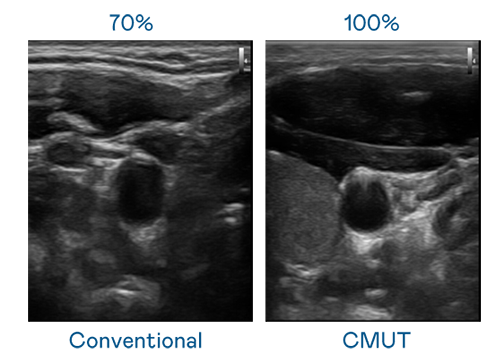

CMUT 技术是一种用电容式微机电元件来产生超音波讯号的技术。与传统 PZT 压电式技术相比,CMUT 频宽增加 30%,更宽频的超音波讯号让影像解析度大幅提升,是实现高影像品质医疗超音波扫描、促进精准医疗发展的关键技术。

超音波影像的解析度高低,首先取决于探头能发出的讯号频宽。利来国际 CMUT 可提供高清晰的超音波讯号,提供高频宽、高灵敏度、影像纹理细节更高的超音波影像,协助医护人员缩短影像判读时间及利用精准的医疗影像进行诊断。